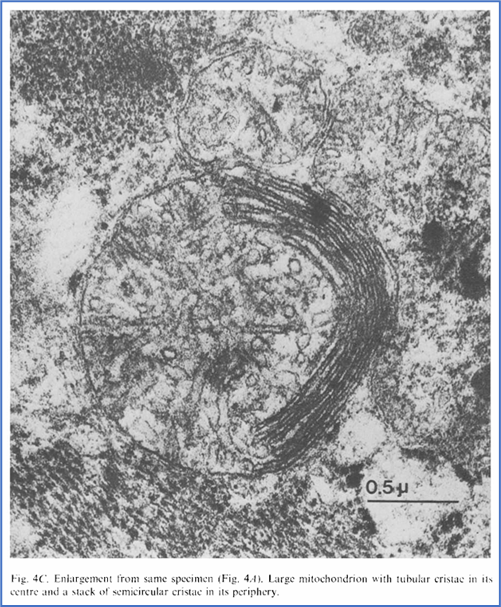

Barth综合征是一种比较“新”的疾病。1983年,荷兰阿姆斯特丹大学医院儿科医生Peter Barth报道了一个跨越五代人的大家系,其中男孩大多在婴幼儿期夭折,有些死于败血症,有些死于心力衰竭。女孩则表型正常。这种遗传模式是典型的X染色体连锁遗传病。Barth认真研究了这个家系,对死亡的患儿进行了尸检,对存活的患儿开展了细致的生化、血液学、和组织学检查。最终发现,患儿肌肉组织中线粒体的结构奇特,且产生能量的关键结构--呼吸链--功能异常 [1]。这一发现让人类第一次认识到X染色体连锁的线粒体病--Barth综合征。

Barth医生拍摄的患儿心肌中异常线粒体的电子显微镜照片。来源:[1]

经过数年探索,如今已基本阐明疾病病因。心磷脂仅在线粒体内膜中从头合成,最初是不成熟的形式,其中脂肪链的长度与饱和度各不相同。随后心磷脂要经过一个成熟过程,在tafazzin等磷脂酰基转移酶的催化下,用亚油酸这种常见的脂肪酸取代不对称脂肪酸,经过多次脱酰基-再酰基化反应,最终形成成熟的、对称的心磷脂 [6]。在健康人的心脏和肌肉细胞中,80%的心磷脂都是这种成熟形式。在Barth综合征患者中,成熟的心磷脂严重缺乏,而大量未成熟的心磷脂累积或被降解。这进一步导致了线粒体内膜嵴结构异常以及呼吸链功能障碍,这是患者出现心脏等器官损伤的核心原因。